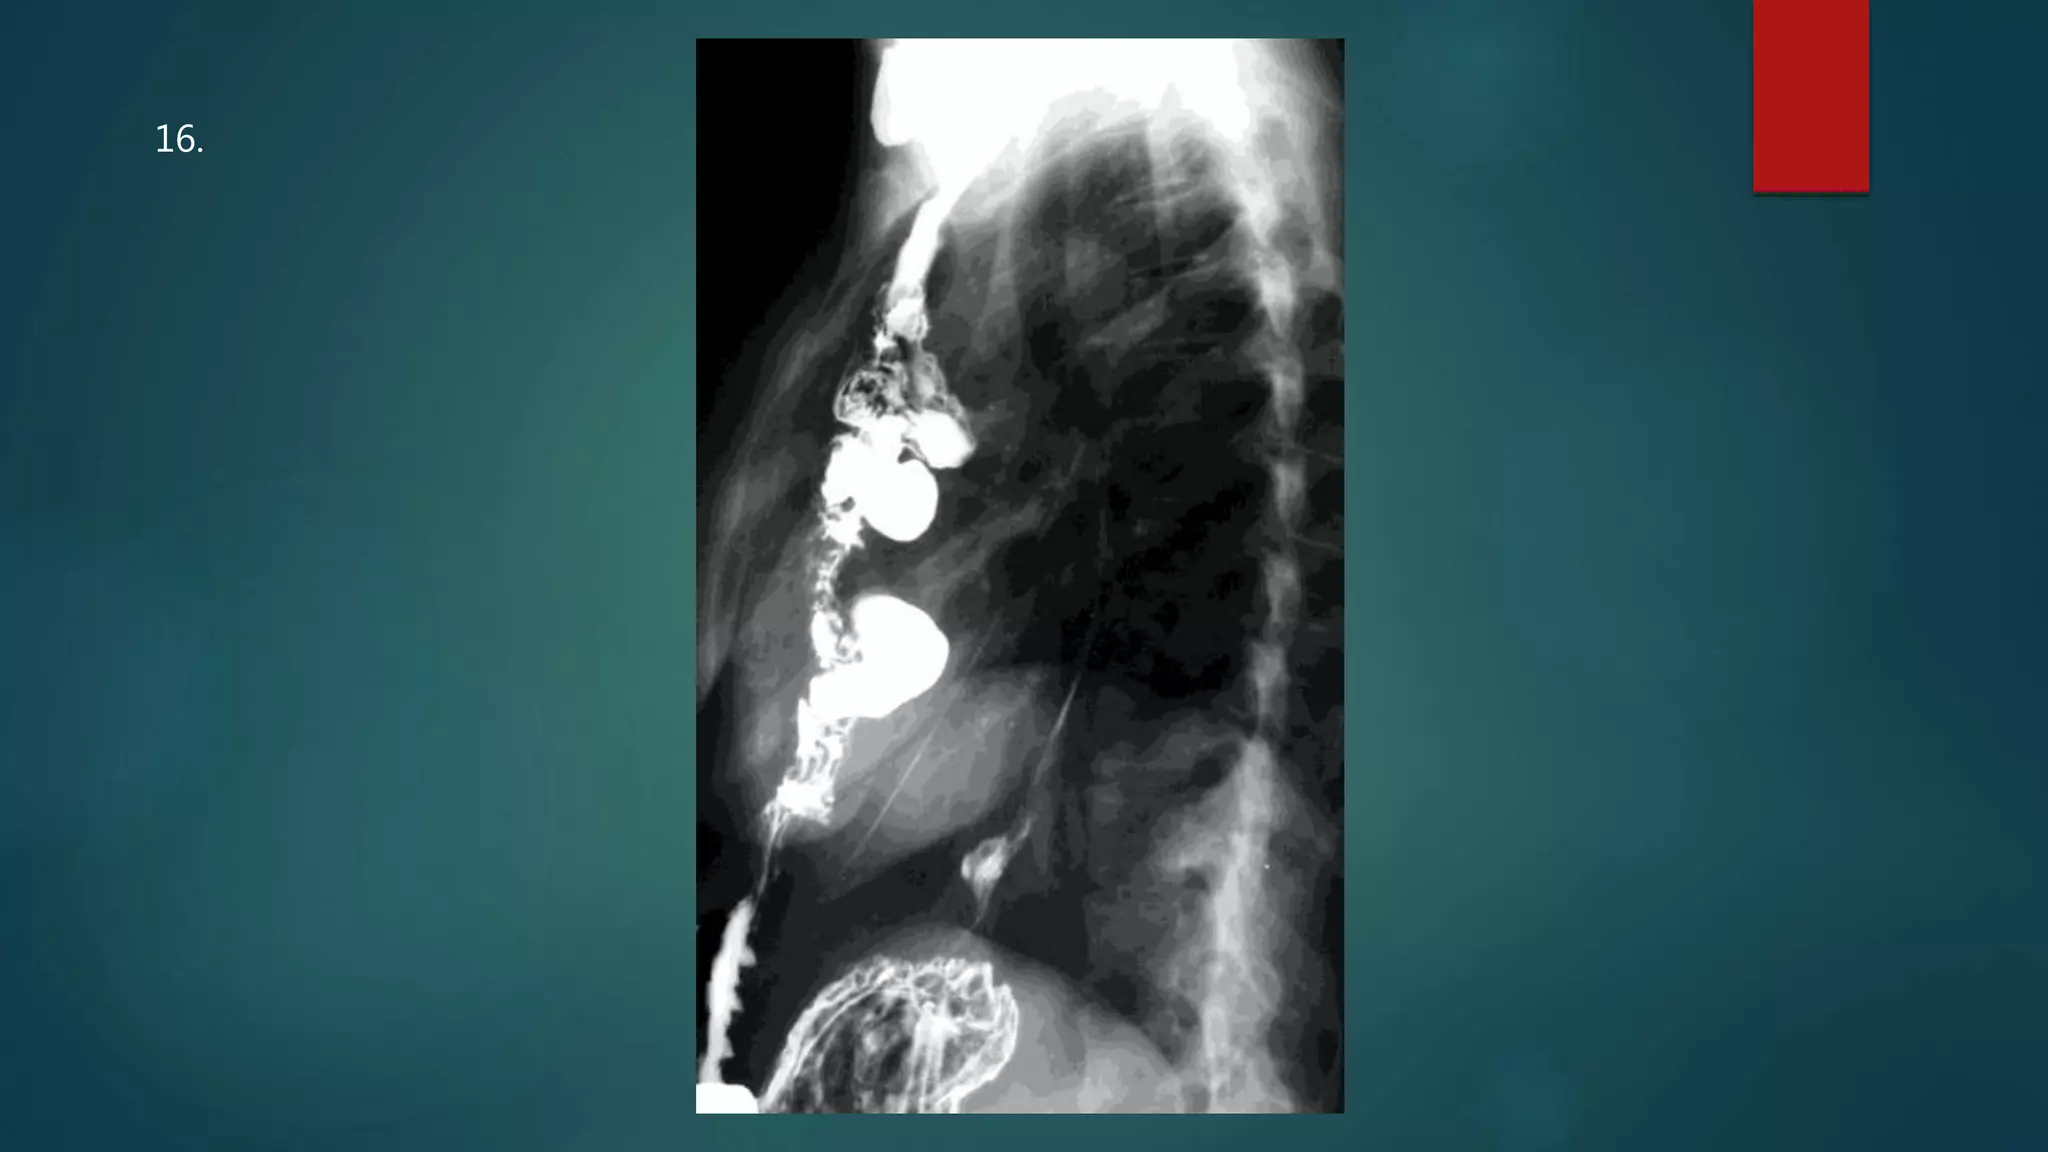

This document appears to be a medical report discussing several patients. It mentions a 35-year-old who was in a severe motor vehicle accident and an 81-year-old with a history of a non-vegetarian diet who had a perforated bowel from a chicken bone. The document provides few other details across its 25 numbered entries and was authored by Dr. Anish Choudhary for junior year 3 on May 30, 2016.